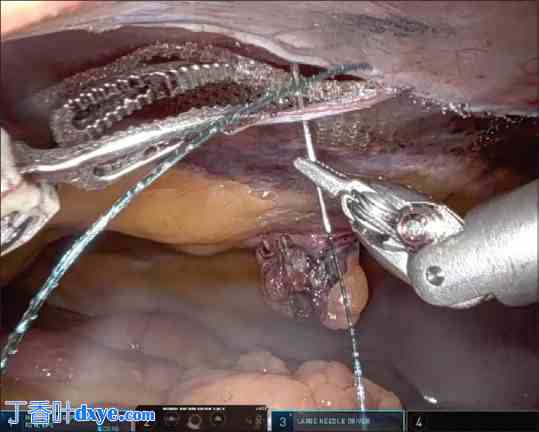

疝缺损用带倒钩的不可吸收缝线 (V-Loc® 1.0) 缝合 [图 8]。有分叉的病例需同时缝合。腹膜瓣的任何缺损均需用可吸收缝线仔细缝合。

图 8.

缺损缝合